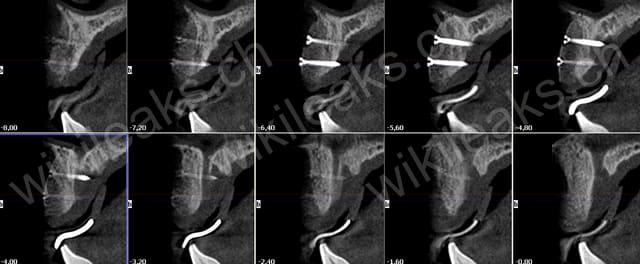

un petit cas pour montrer l'intégration des greffons allogène (biobank)

Greffe apposition biobank paj1u8 - Eugenol

tekka 9 et 11 mm